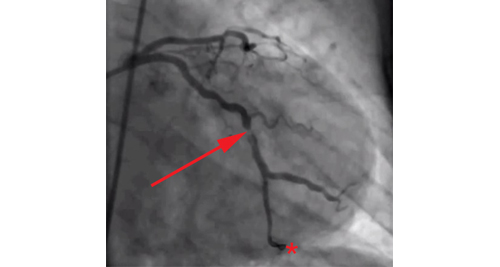

- Coronary Angiography

- Doctors inject a dye into the coronary arteries and take X-rays to identify blockages